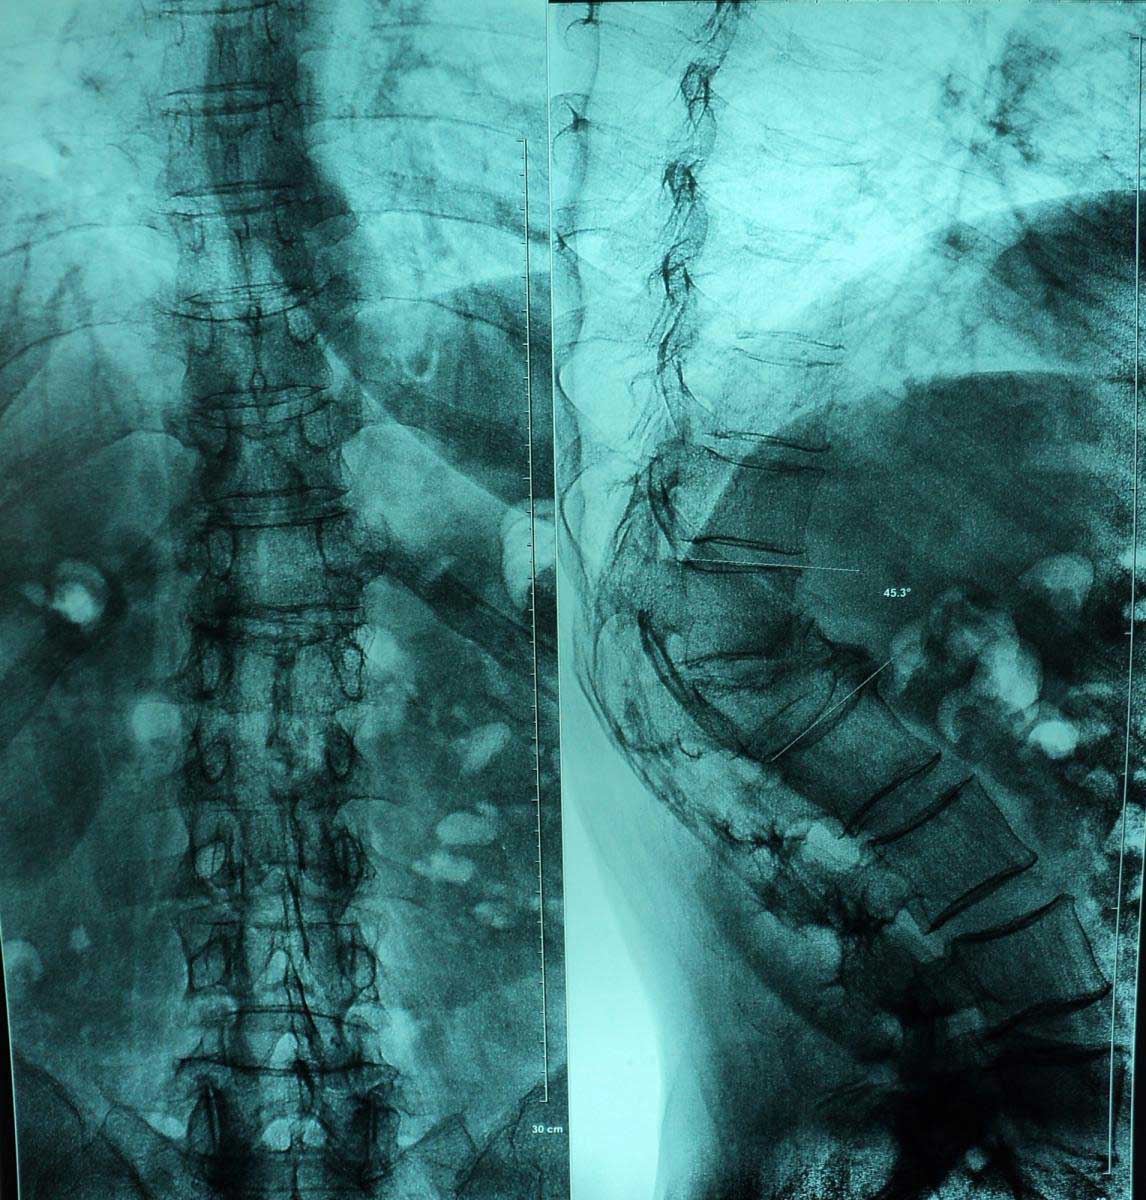

Примеры хирургического лечения перелома в нашем центре:

- рентгенография в двух проекциях;